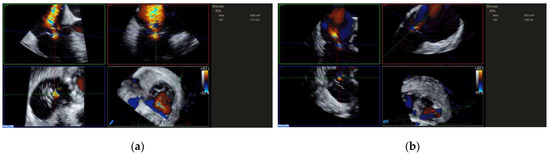

3.5. Valve Function Assessment